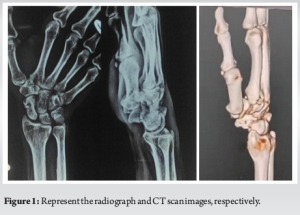

A 58-year-old right-hand-dominant male presented with pain and stiffness in his right wrist, which has been ongoing for several months. The initial injury occurred 8 months ago when he fell onto his outstretched hand. The patient is a non-smoker and has generally been in good health. He was previously diagnosed with a scaphoid fracture and opted for conservative management at the time. However, over the past few months, he has experienced worsening pain and stiffness, which have been affecting his ability to perform daily activities. There is no history of any further trauma since the initial injury. Radiographs revealed a fracture through the waist of the scaphoid, accompanied by a notable humpback deformity. A CT scan was performed to assist in further planning and to confirm the union status of the fracture. In addition, an MRI was conducted to assess for any signs of avascular necrosis in the proximal fragment, which appeared to be within normal limits (Fig. 1). We reviewed the management options with the patient, including the possibility of salvage surgery if the primary intervention failed. A right scaphoid open reduction and internal fixation were performed using Herbert screws, along with a cancellous bone graft harvested from the radius through the same incision. A bone substitute, tricalcium phosphate, was also used. Postoperatively, the patient was placed in a below-elbow slab for a period of 4 weeks (Fig. 2a-d). The patient was started on a range of motion exercises of the wrist and thumb including Handgrip exercises and tabletop exercises. Heavy weight lifting was prohibited for the whole follow-up period. The patient was followed up for a period of 6 months, during which his range of motion showed significant improvement. The DASH (Disabilities of the Arm, Shoulder, and Hand) score decreased from 46 at the time of admission to 8 at the 6-month post-operative follow-up. The patient reported no functional disability at this stage. Six months following the procedure, the patient exhibited good wrist function and grip strength. The range of motion of the wrist increased from 40° of flexion and extension preoperatively to 80° flexion and 70° extension post-rehab. Radiographs showed clear signs of fracture union (Fig. 3).